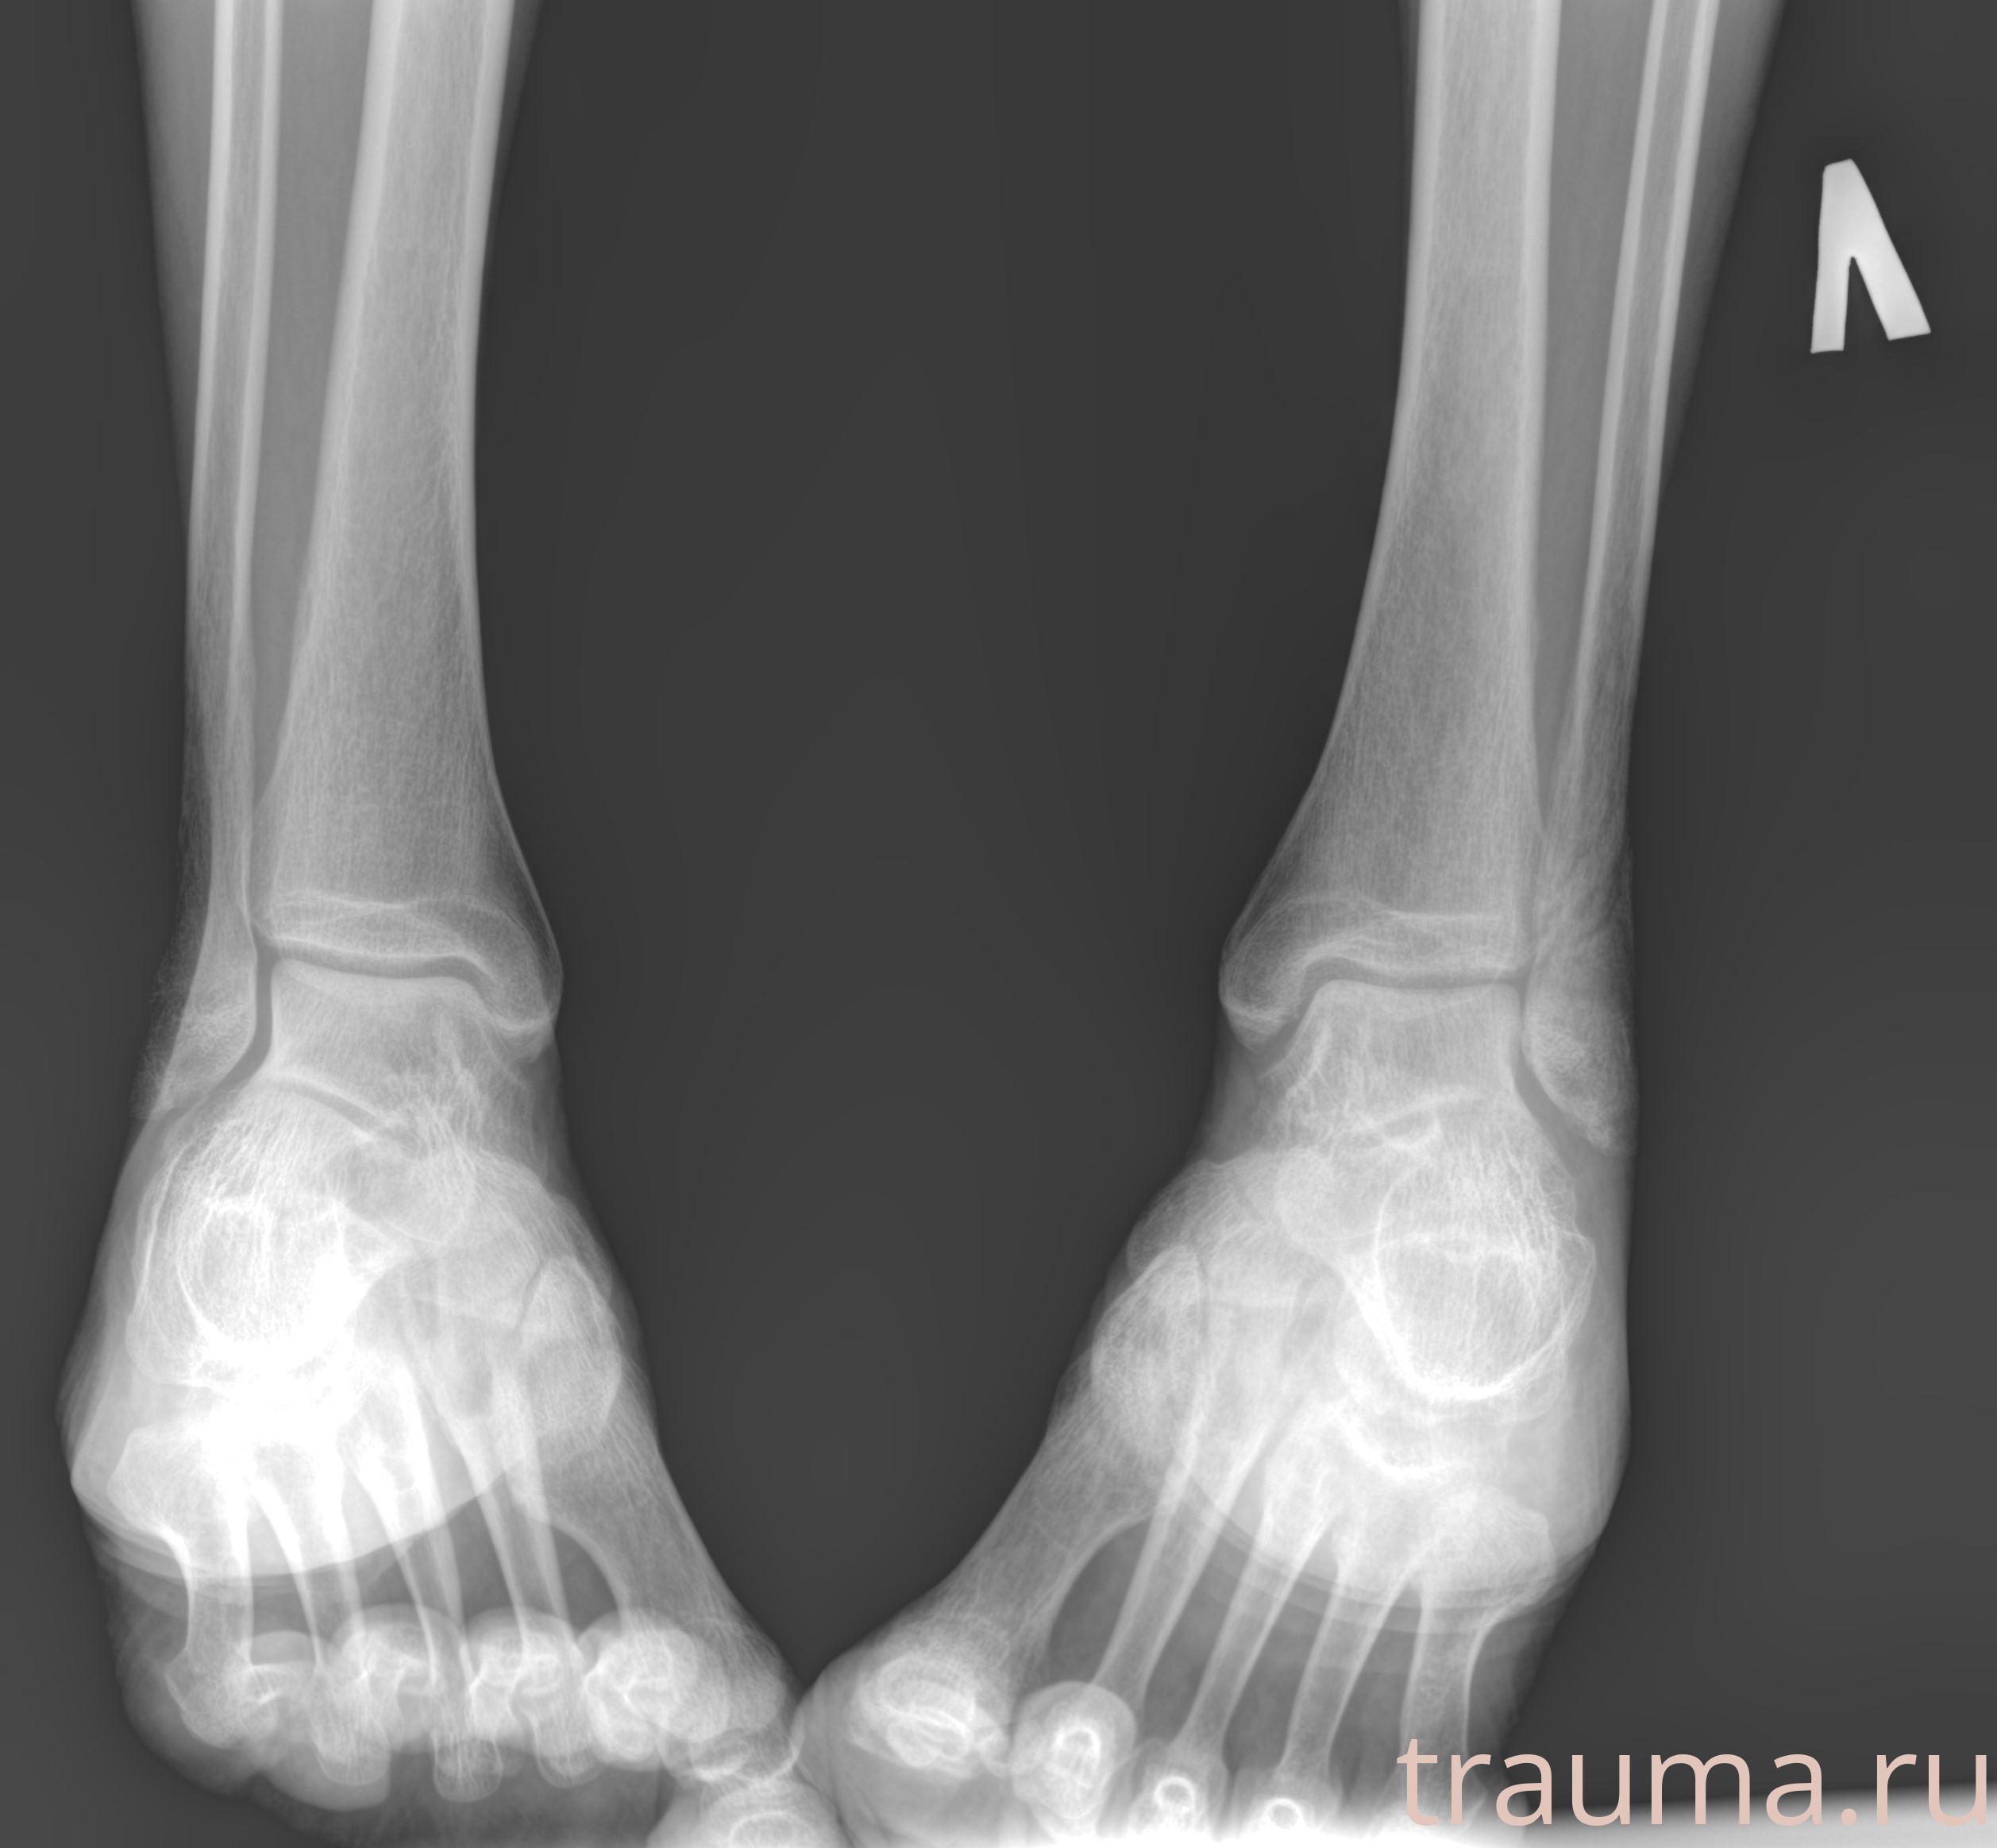

Рентгенограммы

Рентген на дому: по вашему адресу приезжает врач-рентгенолог, травматолог-ортопед с мобильным рентгеновским аппаратом, проводит диагностику травмы или заболевания, делает необходимые рентгенограммы, дает рекомендации по дальнейшему лечению. Получить качественные снимки в домашних условиях возможно благодаря уникальной методике, разработанной МосРентген Центром для института  Склифосовского